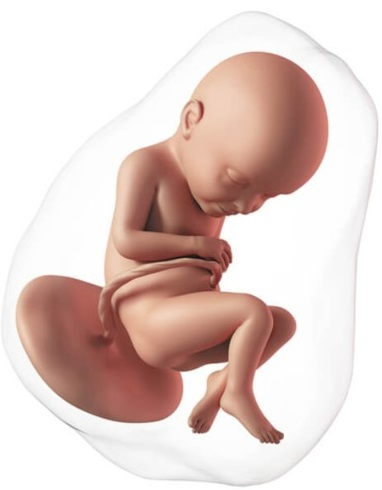

El proceso de la formación del embrión está ya prácticamente finalizado con una longitud de 30 mm. A partir de ahora empieza la etapa fetal, médicamente ya no es un embrión sino un feto. Ya ha completado la formación básica de todos los sistemas.

Ahora ya se mueve con frecuencia, pero son movimientos involuntarios; los músculos todavía tardarán en estar conectados con el cerebro. La cabeza es mucho más grande que el cuerpo, ya tiene orejas, nariz, hasta los párpados, los cuales estarán fusionados durante semanas. Los labios están formados y empieza a abrir la boca. Ya han aparecido pies y manos.

En esta etapa los genitales son exactamente iguales en niños y niñas. Tienen un tubérculo genital que más adelante se diferenciará en la forma de cada sexo. Su piel es translúcida, se puede ver el esqueleto a través de ella. En realidad, los huesos no tienen casi calcio, están formados por cartílago, pero la mayoría de los huesos ya tienen su forma definitiva.